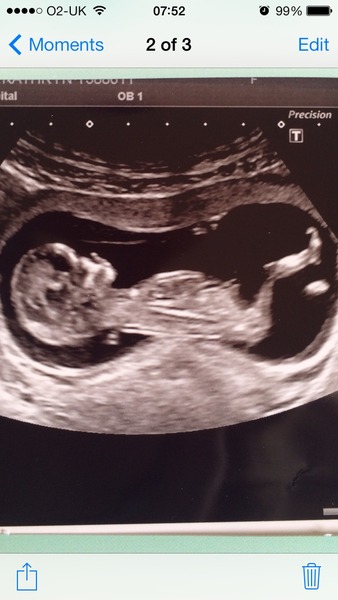

Hi everyone, nice to hear about everyone's scans. Had mine yesterday and all looked well. Bean was being naughty and kept rolling over at the key time so I had to keep jumping around to move it back! Here is the photo.

Twinkle, beautifully clear scan that!!

Hi everyone! I'm new and hoping to join this thread? I'm almost 12 weeks by my reckoning (scan on Tuesday next week) so am due at the end of October. I've been off work with morning sickness for quite a few weeks so am pretty lonely right now- it's hard when you haven't shared your news yet pre-scan and there isn't much communication with the outside world. Will need to catch up with all the messages on this thread but congratulations to everyone and Twinkle, what a brilliant scan picture Smile

Finally got a good pic, still a wriggler today. Nuchal fold was very good so hopefully everything is good on that front too. Wow such a relief.

Lovely scan Twinkletoes. S/he seems to have lovely posture already!

Twinkletoes your scan pic is awesome, I love the shape of babies at this age, when they're all head and belly with skinny stick legs, it amazes me that they can be so fully formed but still so tiny.